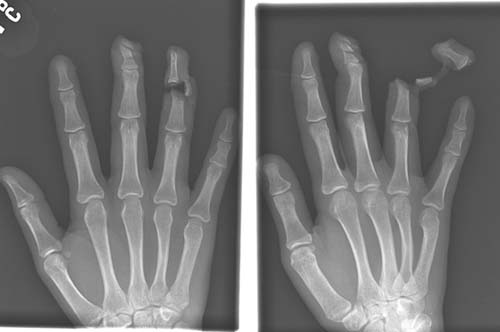

Bıçaklı bir saldırgan tarafından parmağı koparılmış bir kurbana ait röntgen.